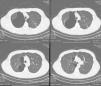

We present the case of a 27-year-old male with a personal history of tobacco habit of 15cigarettes/day for the last 12years, as well as a habitual smoker (3cigarettes/day) of marihuana, who was admitted to our hospital due to chest trauma related to a traffic accident. Emergency thoracic CT without intravenous contrast revealed bilateral apical and paramediastinal bullae, predominantly on the right, with an especially large bulla (13cm×11cm) in the apical segment of the right upper lobe (RUL) and some areas of parenchymal destruction in the subpleural region of the RUL (Fig. 1).

Bilateral apical and paramediastinal bullae, predominantly on the right. A large bulla (133mm×115mm) is seen in the right apical segment. Some areas of parenchymal destruction are also identified in the subpleural region of the right upper lobe, with small bronchiectasis in the posterior apical segment of the left upper lobe, and bibasilar subsegmental atelectasis.